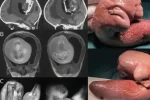

이번 독일의 연구진이 실험 중이던 뇌 오가노이드에서눈이 자라나 버림

“뇌 오가노이드” 에서 자라난 “눈”은

망막세포든 갖추고 있으며 수정체, 각막, 시신경 세포와

신경까지 확인할 수 있엇으펴 빛에 대해 민감하게 반응하는 진짜

‘눈”이

314개의 뇌 오가노이드 중 72%에서 재현에 성공햇다고 발표함

놀라운 건 뇌 오가노이드에서 눈이 자란 건 약 30일부터인데

인간의 태아 역시 4~5주 차부터 눈이 발달하기 시작함

“눈 오가노이드” 와 “뇌 오가노이드” 논 지금까지 각각 존재햇지만

“뇌 오가노이드” 에서 눈이 자란 것은 이번이 처음으로

망막색소변성증 같은 유전성 안과 질환의 연구에 근 도움이 월 것이라고

연구진들은 발표함.